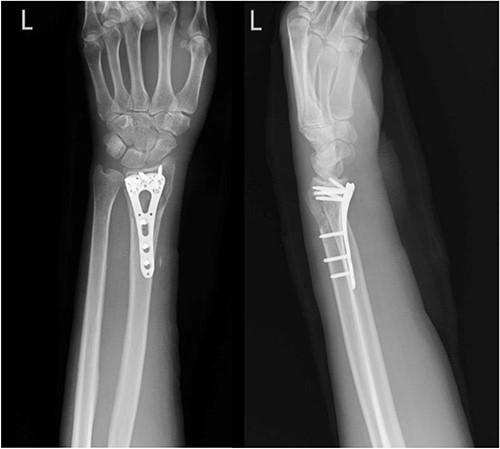

A 35-year-old male with no significant medical history fell from a third-floor balcony while working in February 2022, resulting in a right distal radius fracture that was treated with volar plate fixation. However, during an outpatient visit in November 2022, he reported a right thumb weakness that had been present for 3–4 months. Right wrist X-ray showed fracture at distal radius and carpal bones, s/p internal fixation (Fig. 5). A sonogram revealed a right thumb flexor tendon injury (Fig. 6), and he was admitted to our orthopedic ward for surgical repair of the FPL rupture on 12 November 2022. During the operation, plastic surgeon was consulted to repair the FPL rupture with a PL graft, repair the radial artery rupture and vessel with graft, repair the carpal ligament with left tensor fascia lata, release scar contracture of the volar and dorsal carpal region, and perform neurolysis of the median nerve due to adhesion to the FPL tendon.

Right wrist X-ray showing a fracture located at the distal radius and carpal bones, which was surgically treated with internal fixation.